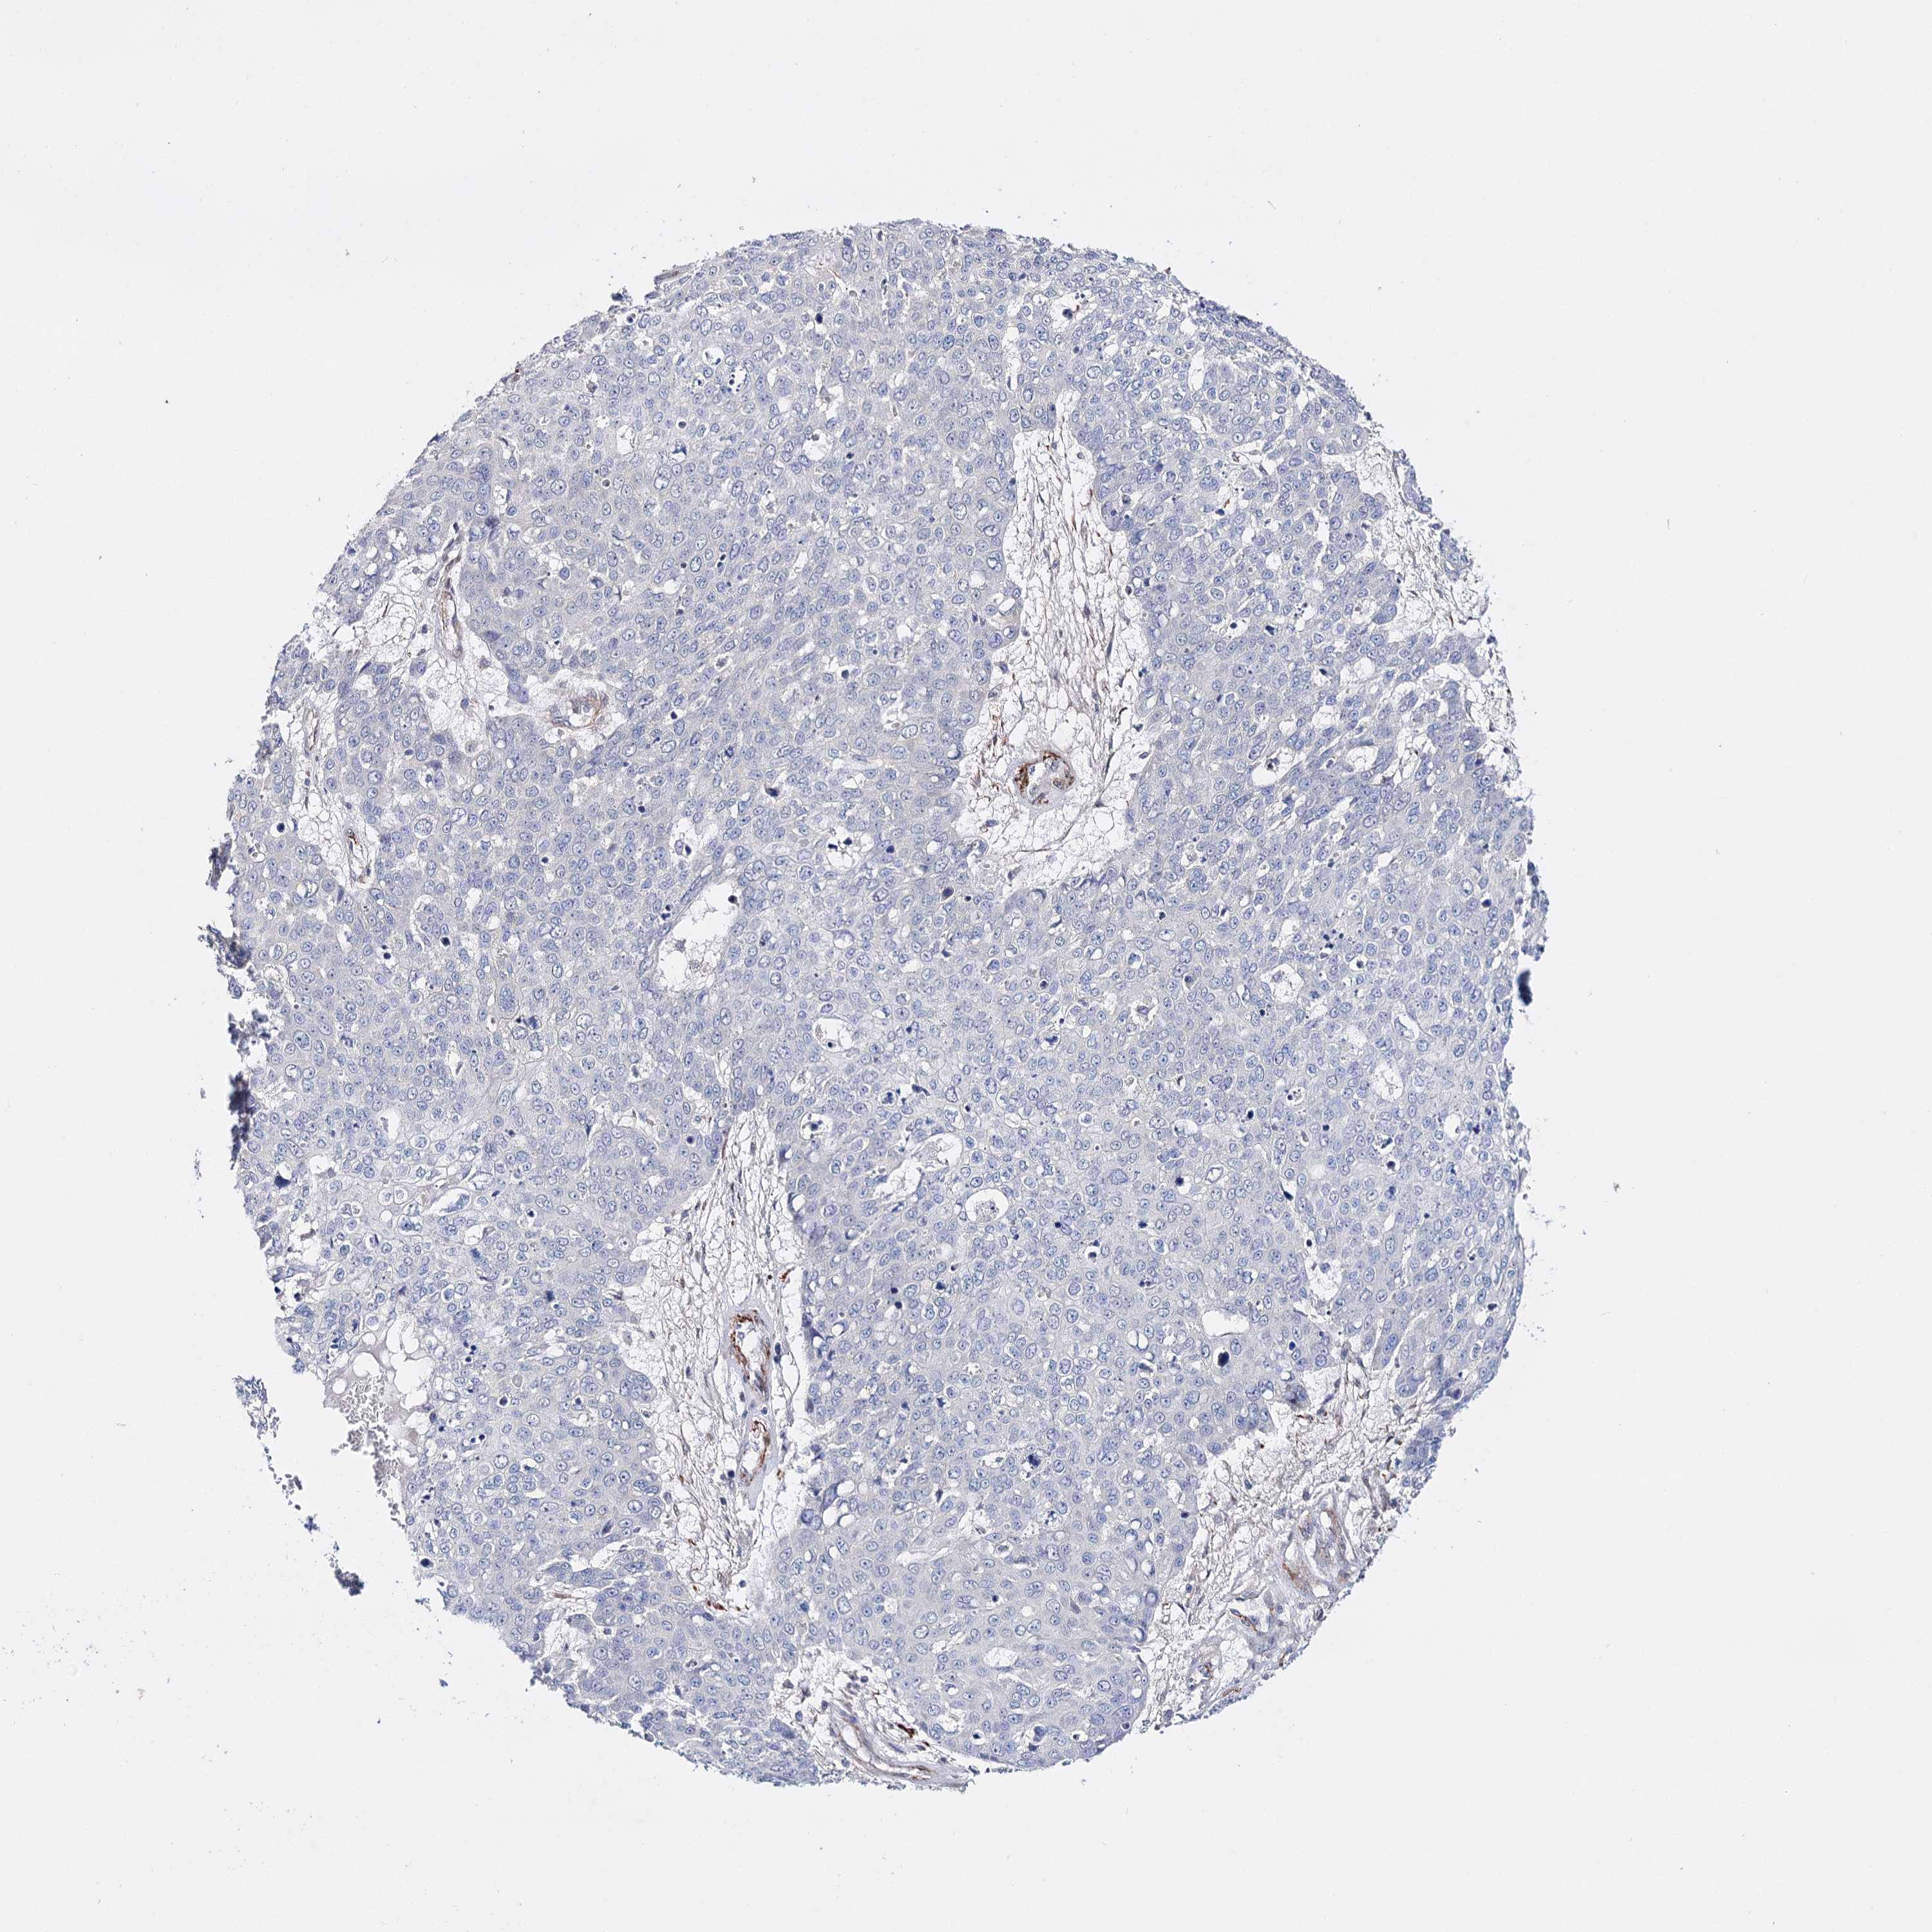

SKIN CANCER - Protein expressioni

A mouse-over function shows sample information and annotation data. Click on an image to view it in a full screen mode. Samples can be filtered based on level of antibody staining by selecting one or several of the following categories: high, medium, low and not detected. The assay and annotation is described here.

Antibody stainingi

Antibody staining in the annotated cell types in the current human tissue is reported as not detected, low, medium, or high, based on conventional immunohistochemistry profiling in selected tissues. This score is based on the combination of the staining intensity and fraction of stained cells.

Each image is clickable and will lead to virtual microscopy that enables deeper exploration of all samples and also displays staining intensity scores, fraction scores and subcellular localization as well as patient and tissue information for each sample.

Antibody HPA037786

Antibody HPA038034

Antibody HPA038867

Antibody HPA038868

Not detected

Negative

<25%

None

Basal cell carcinoma